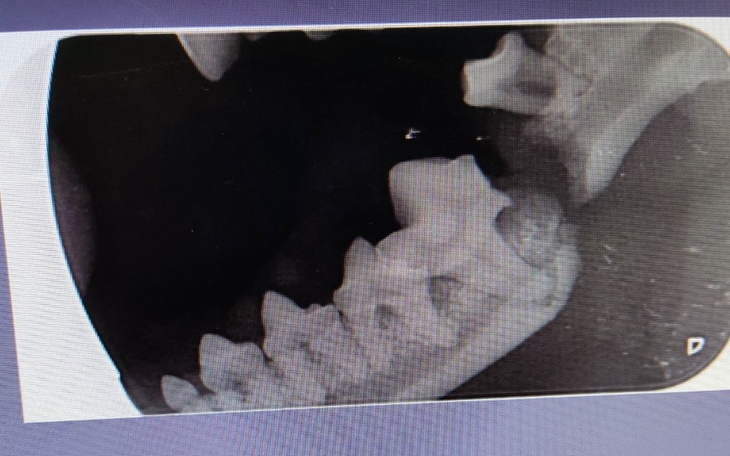

Suczka pojechała na konsultację do pobliskiej kliniki. Zdjęcie RTG nie pozostawiało złudzeń. Szczeka jest pęknięta a w miejscu pęknięcia usunięto tylko pół zęba.

Prawdopodobnie podczas usuwania kamienia zobaczono, że coś nie tak jest z zębem trzonowym i usuwali go ( usunięty jest w połowie. Jednej nie ma. Druga jest w dziąsle) i podczas nieumiejętnego usuwania pękła żuchwa.

Pęknięcie żuchwy nie wyglada na stary uraz. Ze zdjęć wynika, że oprócz konieczności składania szczęki będzie jeszcze sporo pracy z zębami. Mieliśmy ogromne szczęście, bo dzięki uprzejmości lekarzy z zaprzyjaźnionej kliniki nasza dzikuska już jutro będzie miała składaną szczękę.